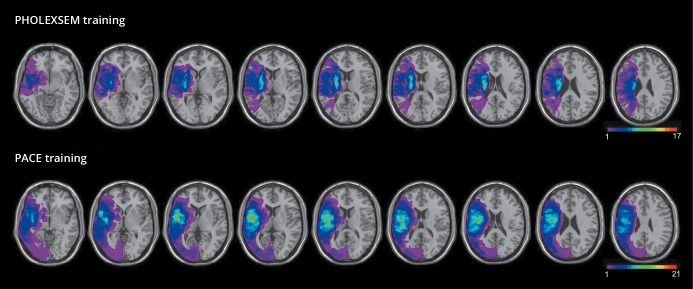

Abstract Image